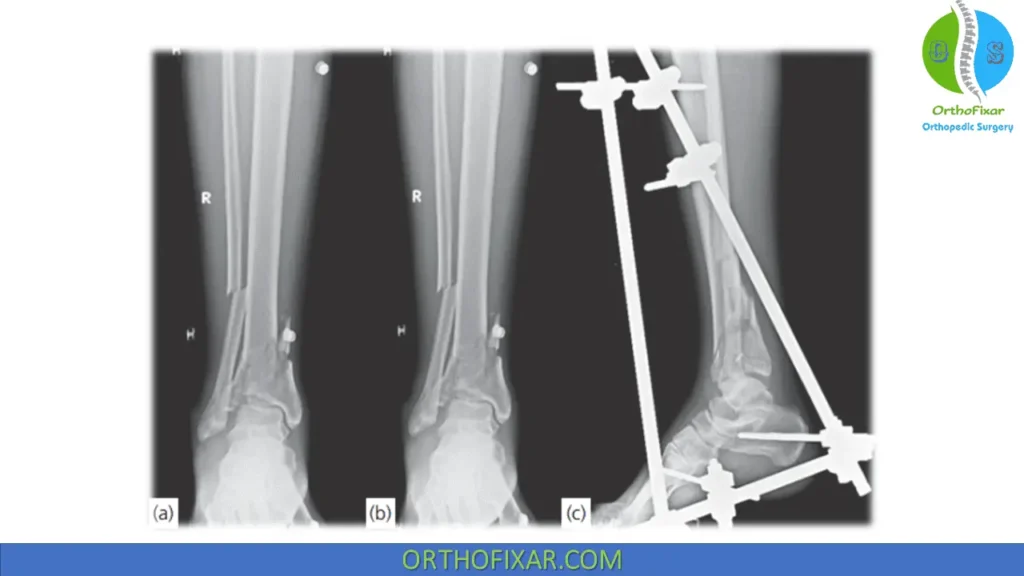

Limited internal fixation with external fixation is not the most effective treatment method for Pilon fractures. If external fixation is performed, thin wire frames are ideal because they can be used to stabilize the articular surface and provide rigid fixation.

Primary temporary external fixation, delayed ORIF is the most commonly used method. Fixation of the fibula is not required at the index operation, because immediate ORIF is associated with an unacceptable rate of wound complications and therefore is not advocated.

ORIF of tibia and fibula is delayed until soft tissue swelling resolves and any hemorrhagic blisters have epithelialized.